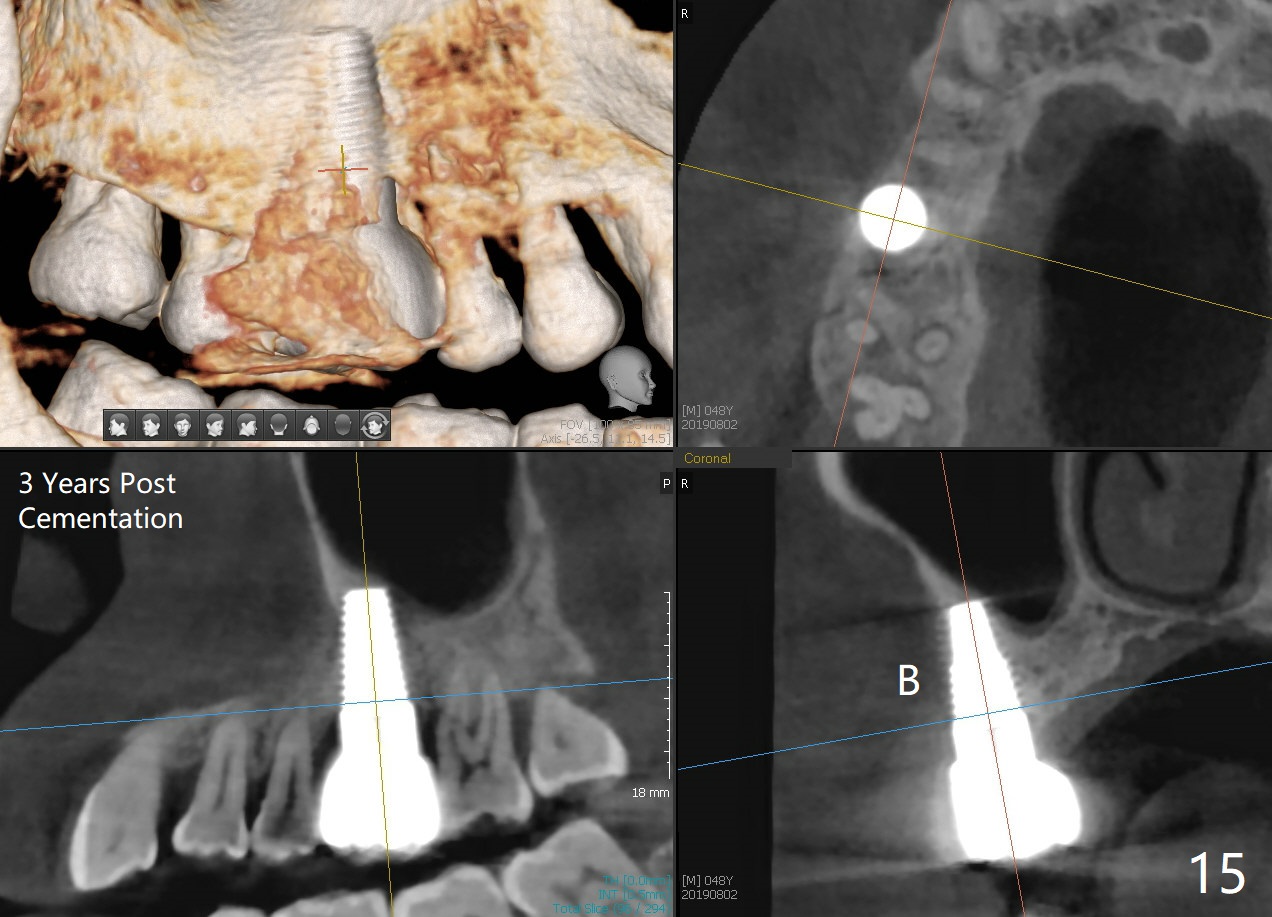

The patient returns for restoration 23 months postop; the implant appears to have been osteointegrated (Fig.14). There is no buccal or palatal gingival recession. The large implant appears to close the large defect readily and enhances bone/implant contact. The buccal plate seems to be thin 3 years post cementation, although there is no sign of periimplantitis (Fig.15). The mesial papilla is severely recessive with open contact 3 years 5 months post cementation. BW shows DO caries of the teeth #2, 4 and 30. The crown is removed for better oral hygiene by fabricating a provisional and conservative composite for #4. Water Pik is recommended.